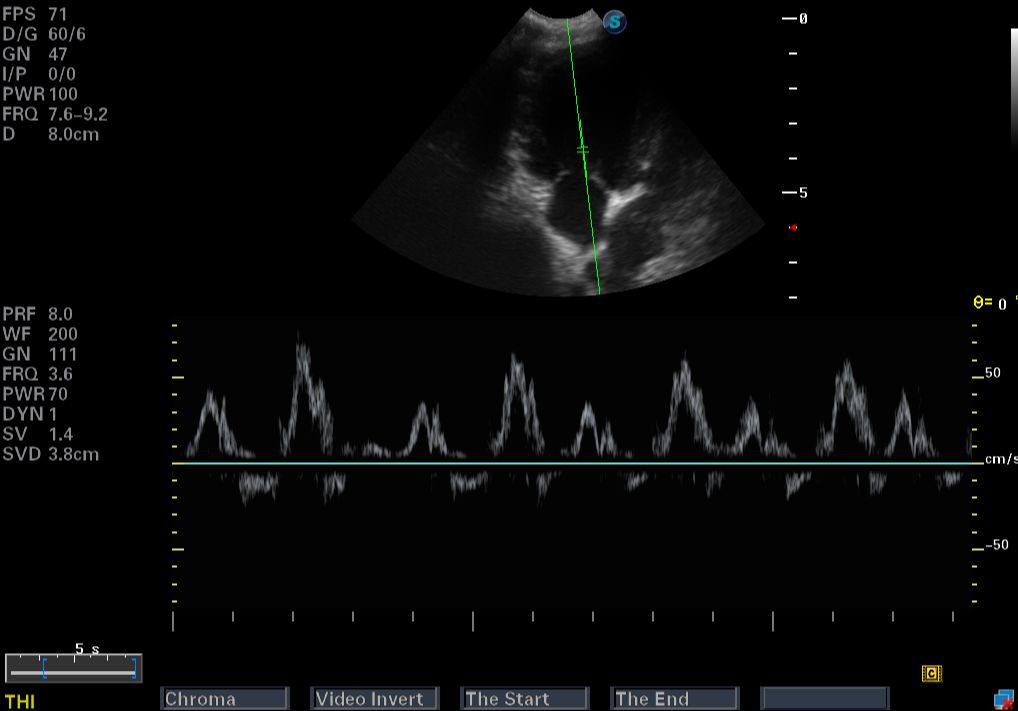

Images from the S9 Pro